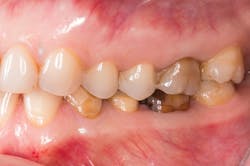

A patient presented with multiple deficient restorations, discolored teeth, and attrition (figures 1–4). The patient’s treatment plan was a full-mouth rehabilitation with a combination of veneers, crowns, and onlays.